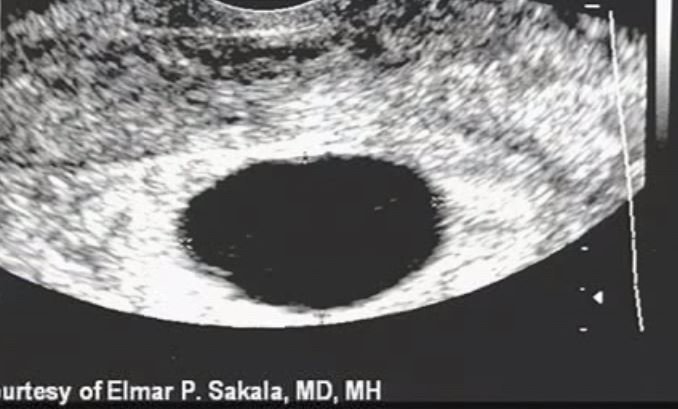

VEamos unos ecos

normal